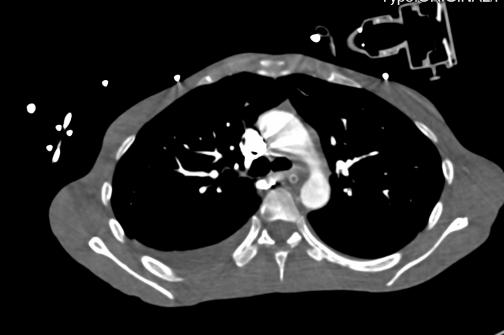

2021-4-29 CTPA:肺动脉干、左右肺动脉及其分支未见狭窄及明显充盈缺损。右肺、左肺下叶见斑片影、磨玻璃影及实变影。

2021-4-29全腹增强CT:腹盆腔散在积液,上腹腔少量积气,腹壁软组织积气,盆腔置管影。肝实质灌注不均,肝内淋巴瘀滞,提示肝功能损害。右侧见一支副肾动脉;左肾动脉提前分支。双侧附件区见多房囊状低密度影,可见环状强化,囊肿?卵泡?或其它?

2021-4-30心脏彩超:右心稍大,三尖瓣少-中量反流,估测肺动脉收缩压约74mmHg。

患者青年女性,慢性病程;主要表现为腹胀、呼吸困难,术后出现意识障碍、II型呼吸衰竭。经呼吸机辅助呼吸、对症支持等治疗后,患者意识恢复但呼吸困难无明显改善;既往有有粉尘接触史。查体见患者极度消瘦、营养不良,双肺呼吸音粗,可闻及散在湿啰音。血气示II型呼吸衰竭、高碳酸血症,轻度贫血,低蛋白血症,电解质紊乱,炎症指标、肌酶、BNP升高,院外腹水检查示漏出液,未见肿瘤细胞;胸部CT:双肺斑片影,抗感染治疗后病灶吸收;腹部增强CT:双侧附件区分别混杂密度团块影,内见多发囊泡影;心脏彩超:右心稍大,重度肺动脉高压。